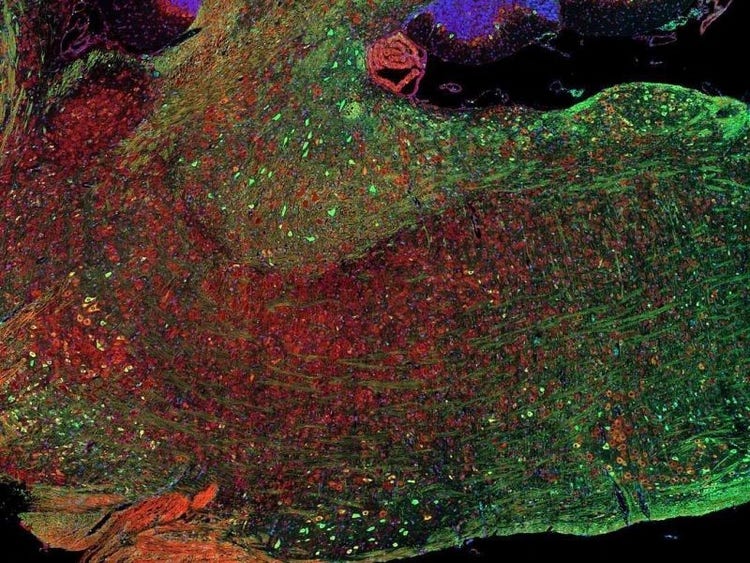

Fluorescence imaging of a mouse brain

これらの画像は一つひとつが独立した拡大画像に見えますが、すべて合わせると、蛍光イメージングで撮影されたマウスの脳の画像が形作られます。

イギリスの科学者、George G. Stokes卿は、蛍石に紫外線を当てると蛍光を発することを最初に発見し、「蛍光」という用語を作りました。Stokes卿は、蛍光は励起光よりも波長が長いことに気づき、今日では、この現象はストークスシフトとして知られています。蛍光顕微鏡法は、自然のまま(一次蛍光または自家蛍光と呼ばれます)か、蛍光を発することのできる化学物質で処理した場合(二次蛍光として知られています)かのいずれかで蛍光を発することのできる物質を研究するための優れた方法です。